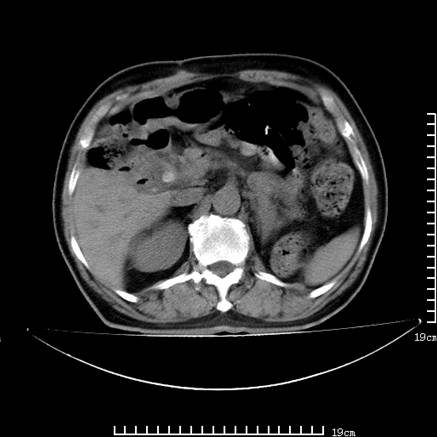

以下是引用lirenxiong在2008-7-19 22:01:00的发言:[br]胆总管结石并胆系感染,胆囊切除术后改变!左肾未见!左肾上腺增生肥大?请全腹扫描,增强!

以下是引用liaoqiang在2008-7-19 22:26:00的发言:[br]胆总管结石伴胆系感染。

以下是引用lirenxiong在2008-7-19 22:01:00的发言:[br]胆总管结石并胆系感染,胆囊切除术后改变!左肾未见!左肾上腺增生肥大?增强!